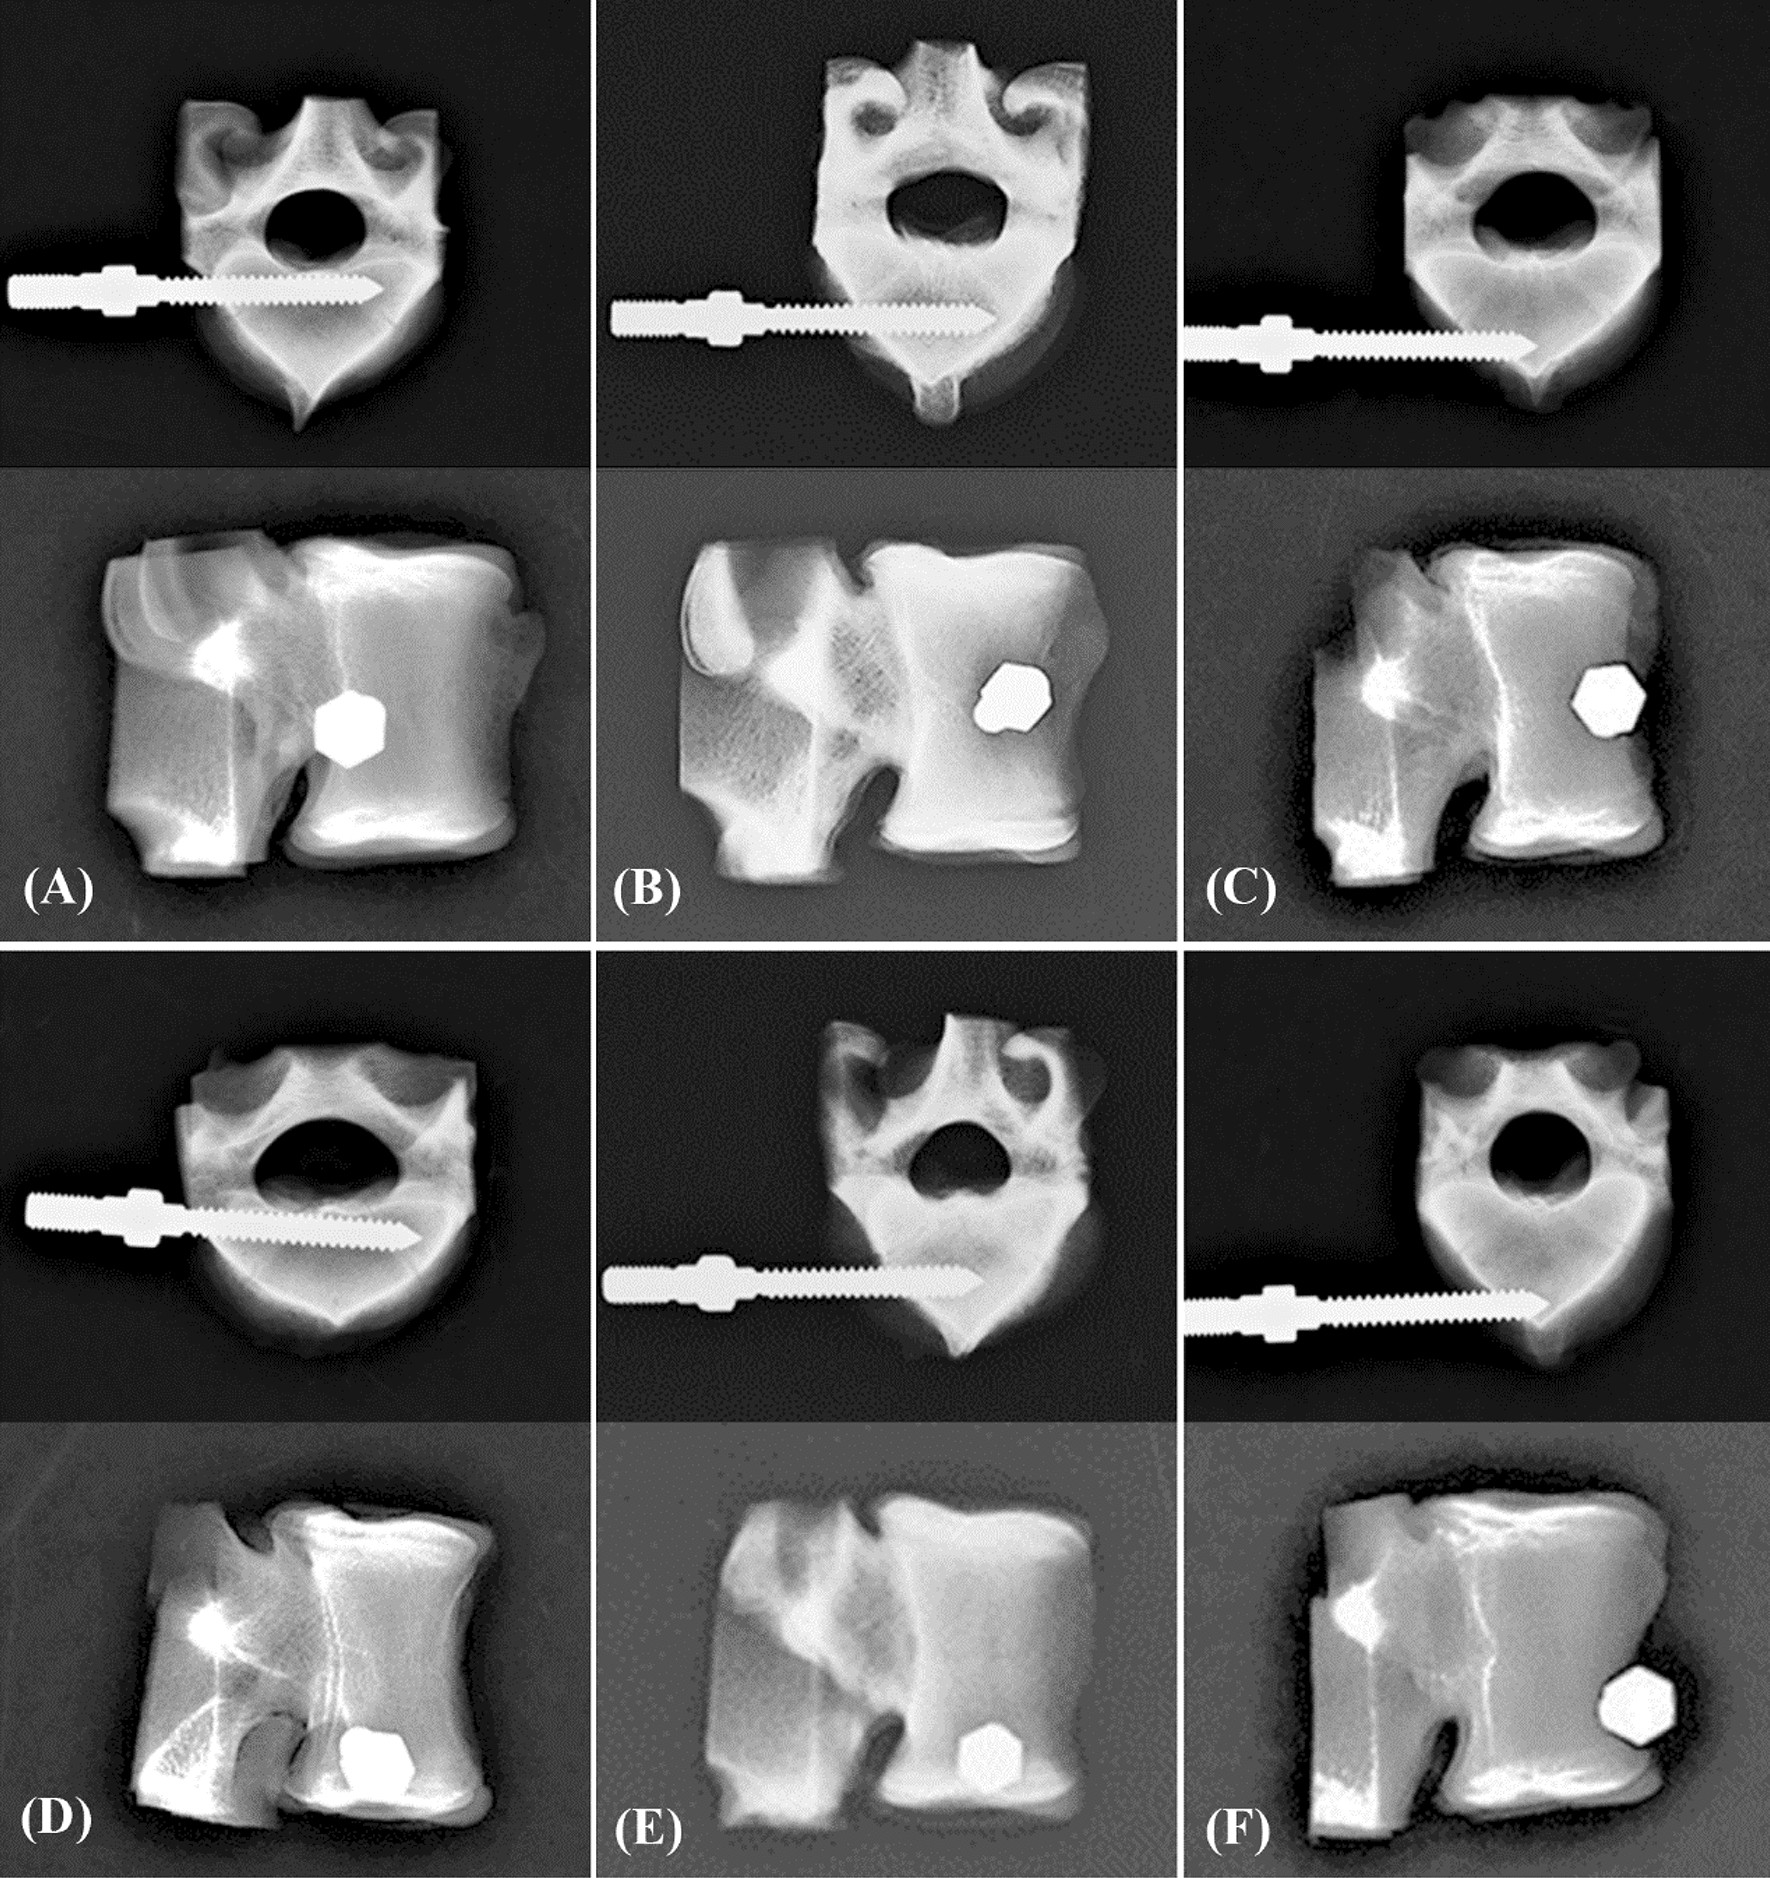

Axial (upper) and sagittal (bottom) X-ray images of the unicortical fixation modality showing the porcine vertebrae with various insertion positions. (A) C-p, (B) C-m, (C) C-a, (D) L-p, (E) L-m, and (F) L-a.